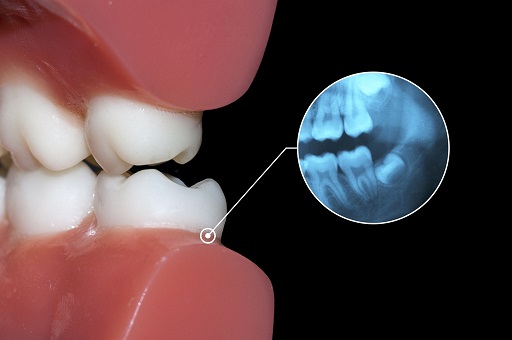

移植成功的智齿,能植根于牙龈中,达到“牙周膜愈合”。

牙周膜是牙齿和牙槽骨之间的一层致密组织,有丰富的神经末梢,能感知食物的大小、软硬,还能缓冲咀嚼对牙槽骨的冲击力。

有牙周膜,方有“咀嚼感”。

优势2:坚固,不易损坏移植成功的智齿会保留牙周膜神经末梢,因此仍有知觉触感,会对咬到的过硬物产生避让反应,避免硬碰硬,损坏牙齿。

智齿能否完整拔出、保留完整的牙周膜,决定了移植后牙齿能否与牙窝重新“链接”,这是移植成功的关键。